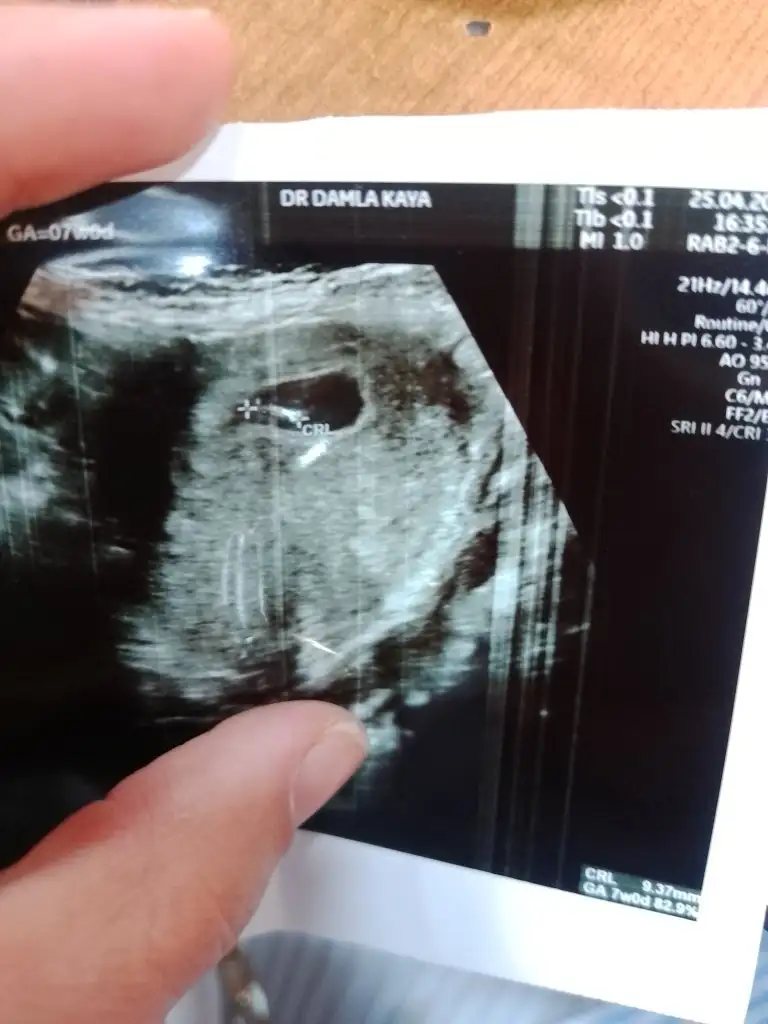

Nub teorisine göre cinsiyet tahmini yapabilen var mııı

7 haftalik 1 oğlum 2 kızım var bu 4. Supriz bir bebek tahminde bulunurmusunuz